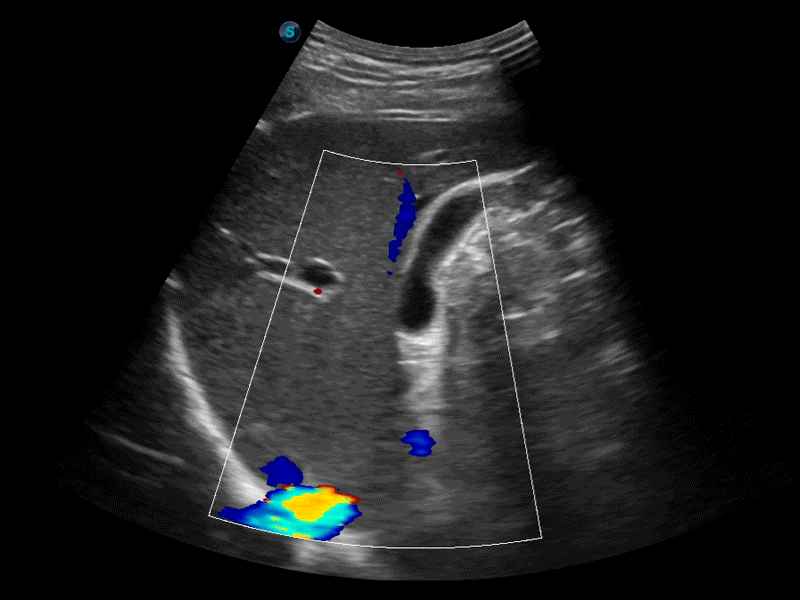

高分辨率血流成像技术提高了对低速血流信号的检测能力。在提高空间分辨率的同时,也克服了血流外溢现象,为用户提供更加真实的血流动力学信息。

凸阵、线阵和相控阵探头进行实时扫描时,开启扩展成像模式,可以扩展超声图像视野,以便更完整地查看大的病灶或组织器官的解剖结构。

通过色彩血流和实时宽景相结合,可观察到完整的静脉或动脉的血流,方便医生检查。实时扫查过程中,如有任何操作失误也可以很容易地进行回扫擦除,而不会中断扫查。